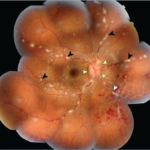

Conjunctival papilloma is a benign squamous epithelial tumor that appears as a fleshy, lobulated, or cauliflower-like mass on the conjunctiva. It may be pedunculated (with a stalk) or sessile (broad-based), and its origin is closely linked to human papillomavirus (HPV) infection, most commonly types 6 and 11.

Color: Pinkish-red or grey-white Texture: Lobulated, gelatinous, or papilliform Surface: May be smooth or irregular with visible central vascular cores

Pedunculated papillomas: Associated with viral etiology, commonly arise from the caruncle, fornix, or palpebral conjunctiva. Sessile papillomas: Common at the limbus; these may be UV-related and have a firmer, broader base.